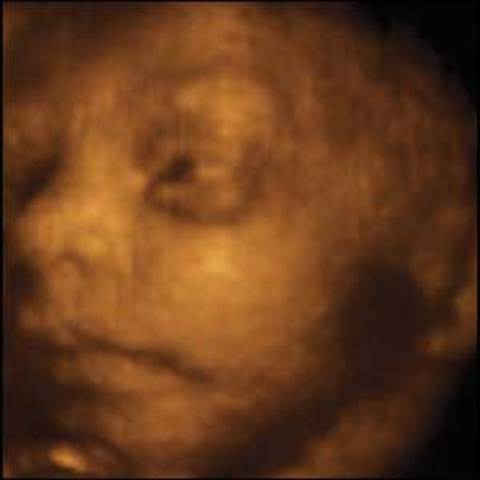

• Baby's Eyes Open (week 21)

Baby's Eyes Open (week 21)

For the first time, the baby's eyes open.